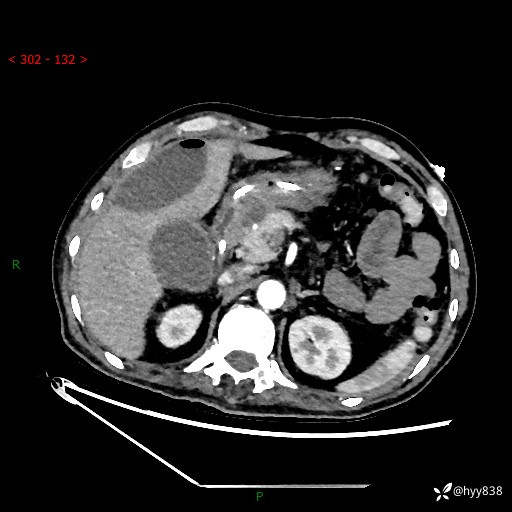

腹部CT平扫

增强